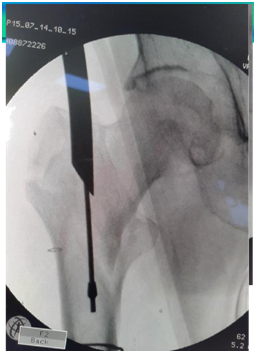

Entry point

1. Dead AP is 10 degree tilt of C arm.

2. Entry by guide wire and special sleeve with multiple options at the trochanteric tip (Figure 9).

Figure 9 Entry by guide wire and special sleeve with multiple options at the trochanteric tip.